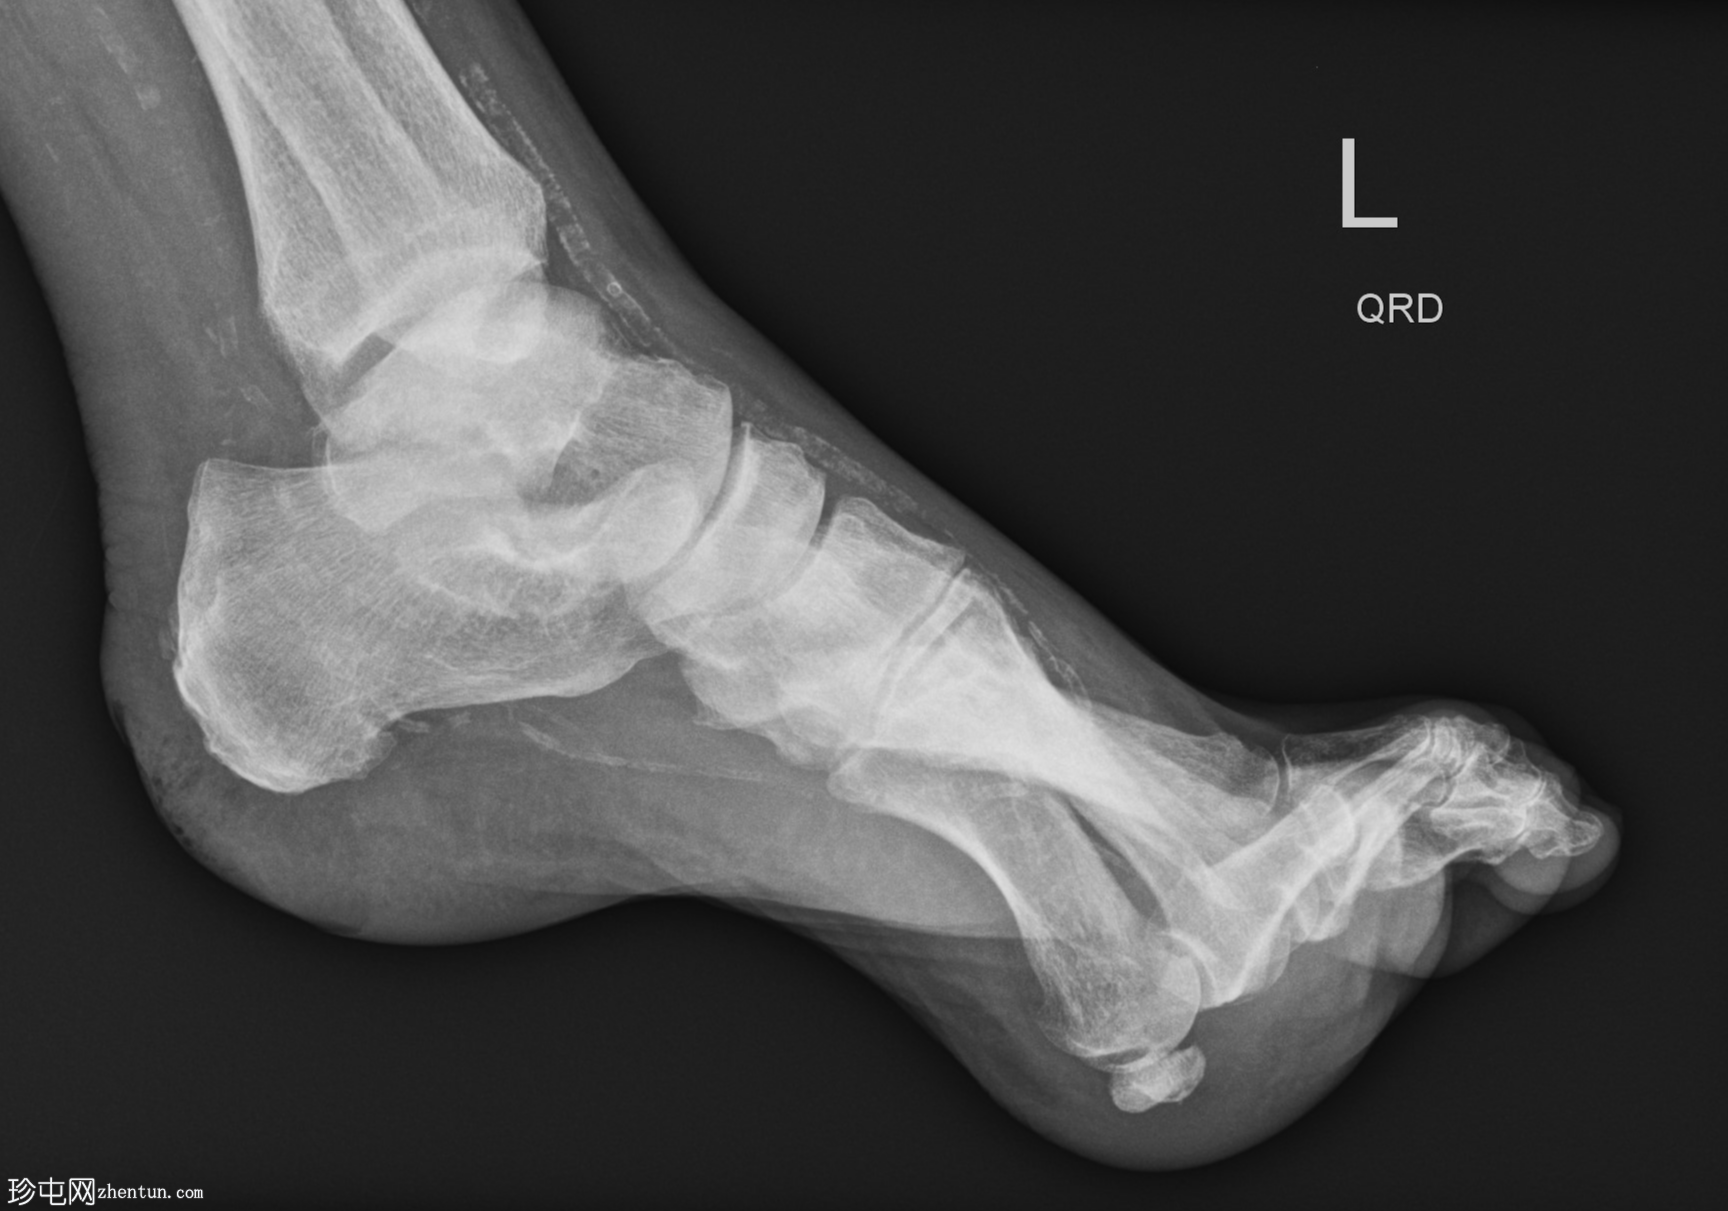

侧位片

跖趾关节爪状趾畸形

动脉钙化

爪状趾畸形是指小趾跖趾关节过度伸展,导致近端指间关节(PIP)和远端指间关节(DIP)屈曲。